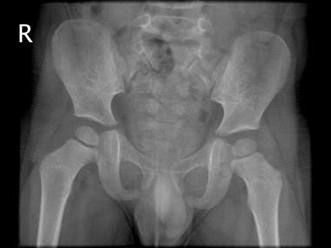

男,请根据其正常盆腔影像图像,判断其最可能的年龄 ( )A、3岁左右B、9岁左右C、12岁左右D、6岁左右E、15岁左右

问题 男,请根据其正常盆腔影像图像,判断其最可能的年龄 ( )

选项 A、3岁左右 B、9岁左右 C、12岁左右 D、6岁左右 E、15岁左右

答案 A